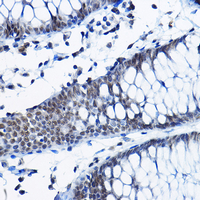

Immunohistochemical analysis of RPP25 staining in human colon formalin fixed paraffin embedded tissue section. The section was pre-treated using heat mediated antigen retrieval with sodium citrate buffer (pH 6.0). The section was then incubated with the antibody at room temperature and detected using an HRP conjugated compact polymer system. DAB was used as the chromogen. The section was then counterstained with haematoxylin and mounted with DPX.